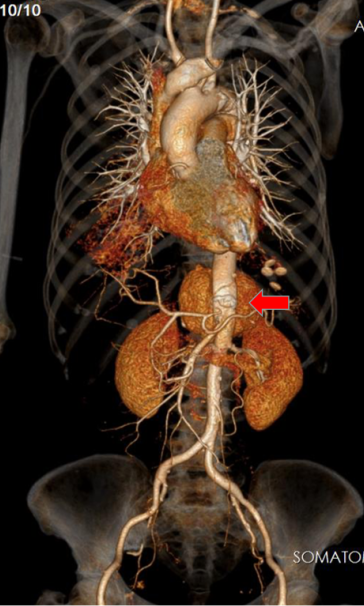

该患者的主动脉假性动脉瘤累及内脏区,病变十分罕见,一旦瘤体破裂患者即可休克猝死(图 1)。由于其外科开放手术的复杂程度远超过单纯的肾下腹主动脉瘤,手术首先需要胸腹部联合切口,之后采用人工血管置换腹主动脉,还要重建腹腔干,肠系膜上动脉及双肾动脉。

图 1